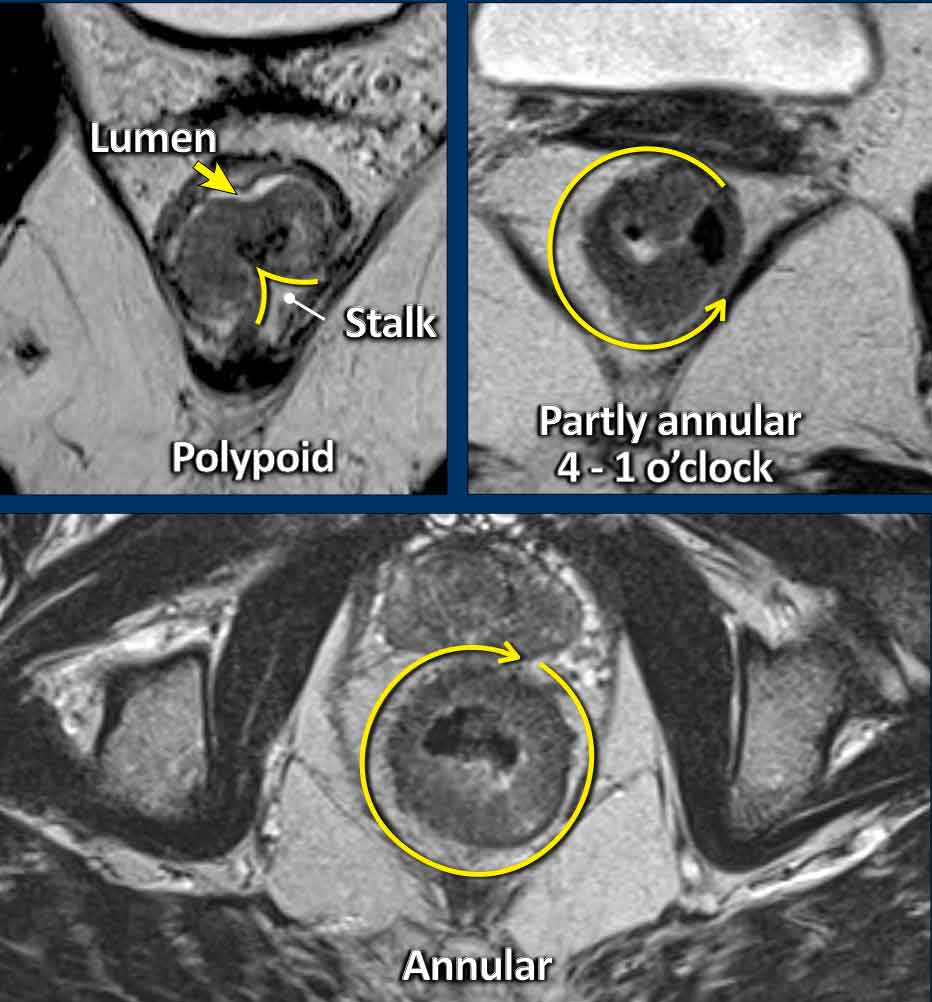

Morphology

Polypoid and Sessile tumors

Rectal adenocarcinomas usually originate from adenomas, which may be:

• Polypoid: Raised on a stalk or focal attachment, often low-grade (T1–T2), projecting into the lumen.

• Sessile: Flat, broad-based, typically presenting as partial or complete annular wall thickening.

Invasive Margin: The tumor’s attachment site to the rectal wall—the invasive margin—is the site where the tumor may invade beyond the rectal wall, and is therefore critical for T-staging and assessing extramural extension.

Tumor Circumference: Describe the degree of wall attachment in the report using either:

• Clock-face notation (e.g., “from 3 to 7 o’clock”)

• Prose (e.g., “left anterolateral”).